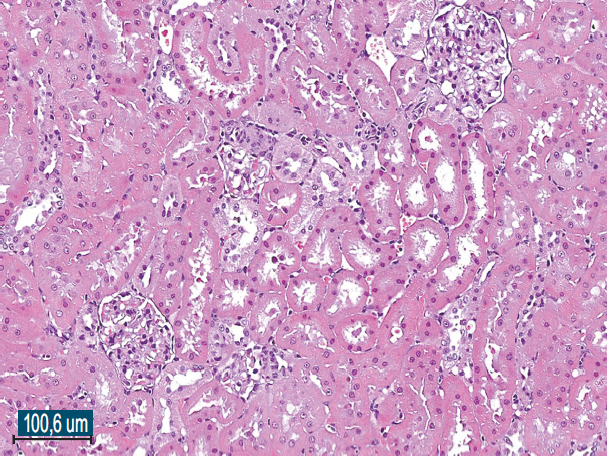

Histological examination of the removed paraurethral cyst was performed (Fig. 6–8).

Fig. 6.The wall of the paraurethral cyst, surgical material. Hematoxylin-eosin staining, ×100. The cyst wall is represented by fibrous tissue with moderate chronic inflammation, fresh hemorrhages (intraoperative) and covered with a transitional epithelium

Рис. 6.Стенка парауретральной кисты, операционный материал. Окраска гематоксилином и эозином, ×100. Стенка кисты представлена фиброзной тканью с умеренно выраженным хроническим воспалением, свежими кровоизлияниями (интраоперационными) и покрыта переходным эпителием